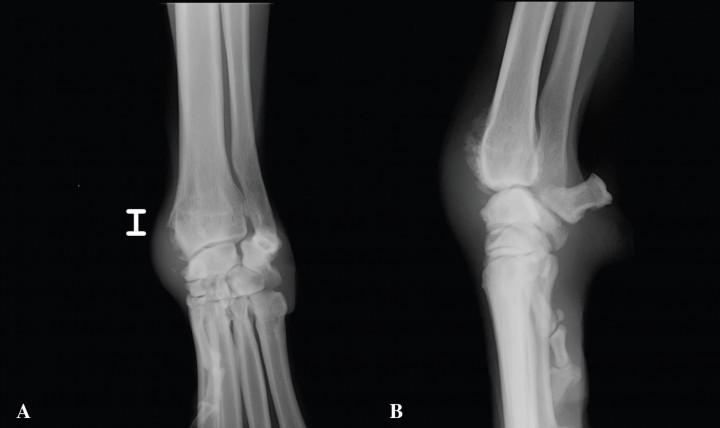

Se realizan dos proyecciones ortogonales de la región del carpo izquierdo incluyendo mitad distal de cúbito y radio (Fig. 1).

<p>Radiografías. A. Anteroposterior (AP), B. Medio Lateral (ML), de carpo izquierdo.</p>

Radiografías. A. Anteroposterior (AP), B. Medio Lateral (ML), de carpo izquierdo.